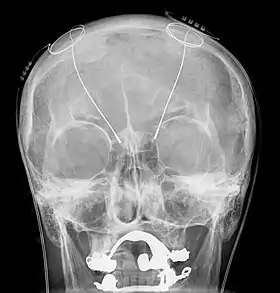

_presenile_onset.jpg.webp)